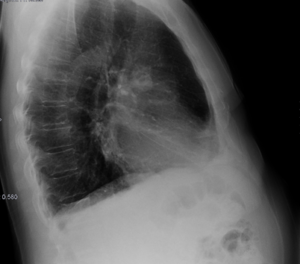

Radiografías de tórax en proyección posteroanterior y en proyección lateral (bipedestación).